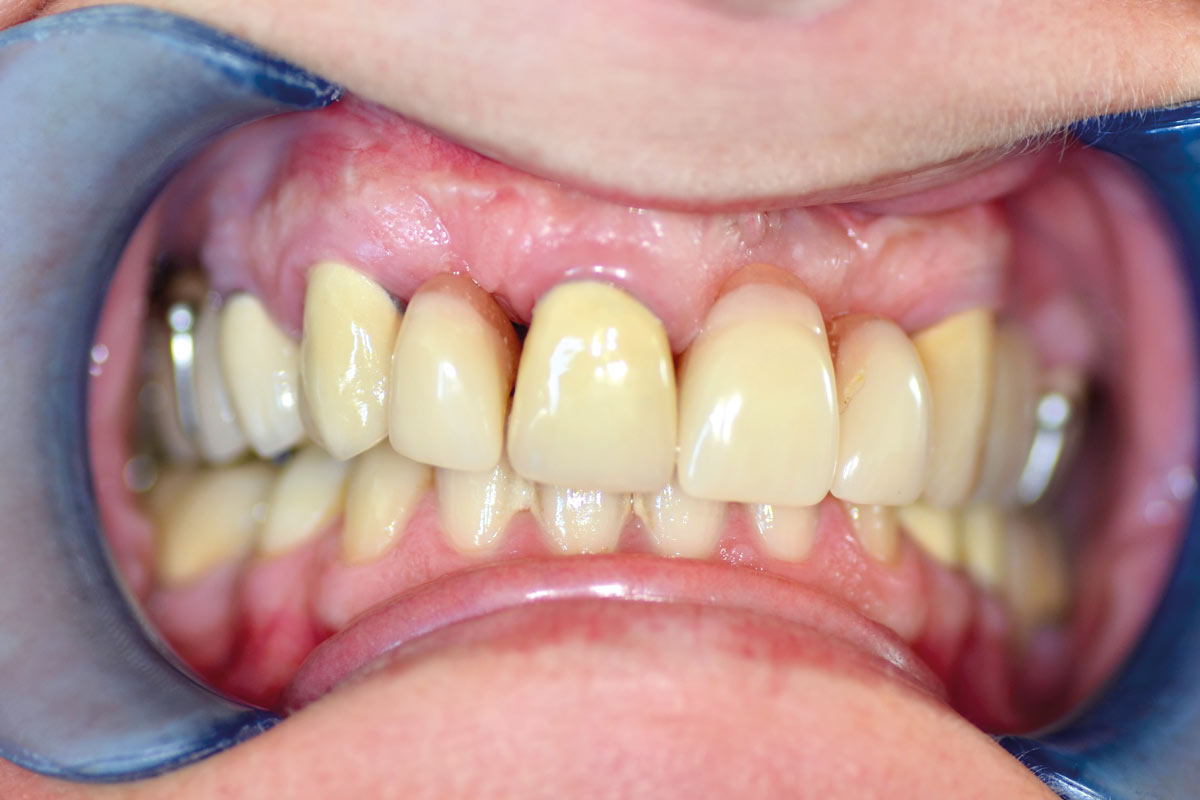

Initial view of the case. Discoloration of 1.1 and mild class I gingival recession